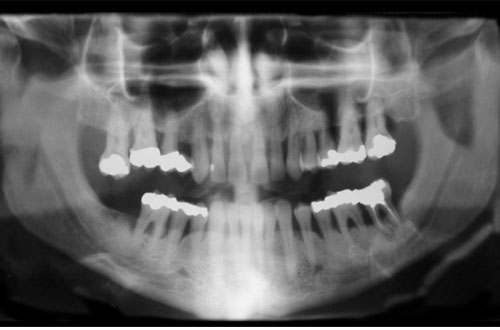

Allvarlig tandlossning

tandlossning